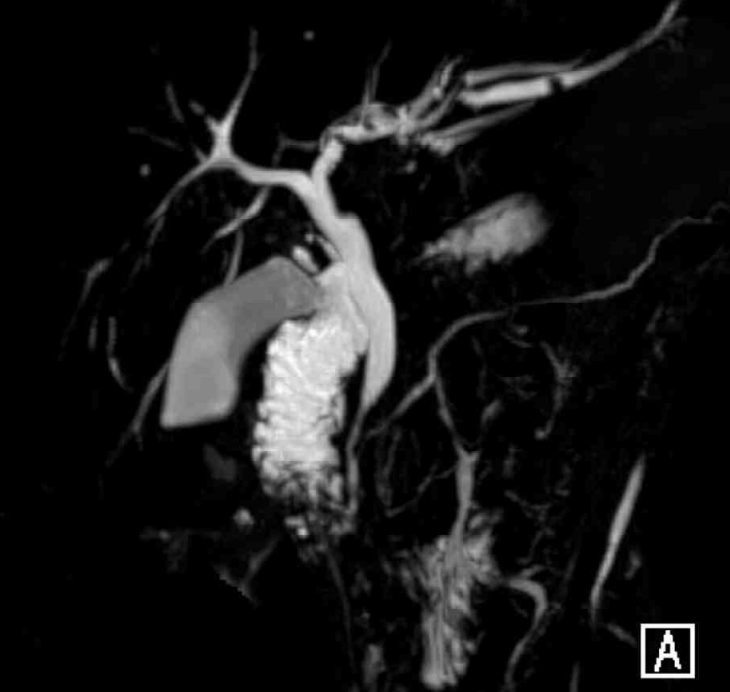

53세 여자가 1일 전부터 배가 아파서 응급실에 왔다. 5년 전부터 1년에 두세 번씩 같은 증상이 있었으며, 그때마다 항생제로 치료를 받은 후 좋아졌다고 한다. 혈압 100/60 mmHg, 맥박 110회/분, 호흡 19회/분, 체온 38.6 °C이다. 공막이 노랗다. 왼쪽 윗배에 압통이 있으나 반동압통은 없다. 혈액검사 결과는 다음과 같다. 복부 컴퓨터단층촬영 사진과 복부 자기공명담췌관조영 사진이다. 치료는?

MRCP: Left intrahepatic bile duct stricture

• CT상 간 좌엽에 하얀 담석과 간내담관의 확장 소견이 관찰되며, MRCP상 left intrahepatic bile duct의 stricture 소견이 관찰된다.

• 임상증상, 혈액검사, 영상소견을 종합할 때 간내담석으로 인해 담관염이 발생된 것으로 생각된다. 환자는 5년 전부터 같은 증상이 반복되었으며, MRCP상 간내담관의 협착 소견이 확인되므로 담관염이 만성적으로 재발함을 알 수 있다. 따라서, 간내담석에 의한 재발성 화농성 담관염(recurrent pyogenic cholangitis)으로 진단가능하다.

•간내담석에 의한 재발성 화농성 담관염의 치료는 간내담석의 위치, 해부학적 소견 , 환자 상태 등에 따라 결정된다. 현재 간내담석이 left lobe에 국한되어 있으며, MRCP상 좌측 간내담관에서 협착 소견 또한 확인된다. 환자가 잦은 재발 hx가 있으며, 현재 수술을 진행하기 어려운 기저질환이나 기저상태가 없으므로 수술적 간절제를 고려하는 것이 가장 적절하다.

• 재발성 화농성 담관염의 치료로 ERCP, PTC, hepatic resection이 고려될 수 있다. 위 세가지 치료법은 담석의 위치, 해부학적 소견, 환자의 상태 등에 따라 결정되는데, 담도 협착(biliary stricture)이나 엽 위축(lobar atrophy)이 동반된 일측성 간내담석 환자에게선 수술적 절제가 고려되어야 한다.